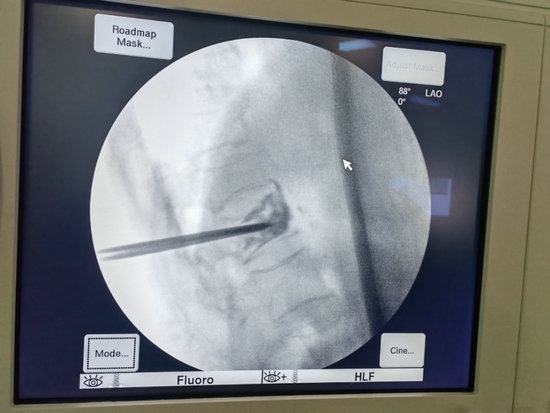

经皮穿刺椎体骨水泥成形术是一项在局麻下即可完成的手术,仅需要在背部伤椎相对应的位置切2个1cm左右的小口,然后将穿刺针穿刺到椎体前1/3的深度。

在透视确认位置良好后,即可注入骨水泥,待确认骨水泥完全凝固后,去除穿刺针,包扎伤口,手术就结束了。